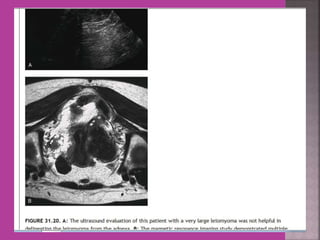

Degeneration Of Fibroid

Cystic Degeneration of

Fibroid

 Study ofnormal uterus and adnexa – with aim to have clear image of normal myometrium, endometrium , ovary and follicles within the ovary.  Myoma—to differentiate myoma from adenomyoma.localization of myoma—sub serous/ intra mural or sub mucous.  Adenomyosis---accurate diagnosis.  Congenital uterovaginal anomalies— bicornuate, septate,subseptate , unicornuate, didelphys ,rudimentary horn and vaginal atrasia etc